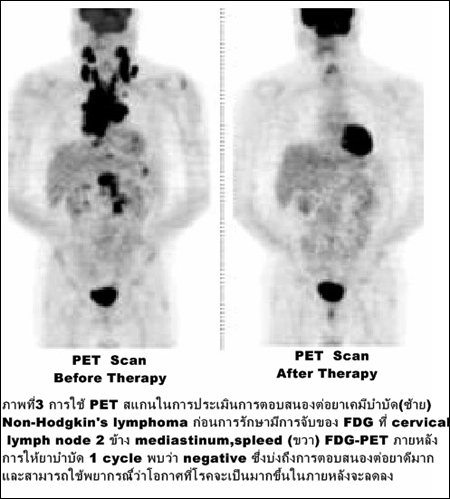

การติดตามผลการรักษาเพื่อเลือกยาโดยเฉพาะยาเคมีบำบัดว่ามะเร็งมีการตอบสนองหรือไม่ (ภาพที่ 3)

และสมควรเปลี่ยนยาหรือไม่โดยจะเห็นการตอบสนองก่อนการเปลี่ยนแปลงขนาดโดยอัลตราซาวนด์, เอกซเรย์คอมพิวเตอร์หรือการตรวจคลื่นสะท้อนสนามแม่เหล็ก (MRI) นอกจากนี้ยังใช้ในการติดตามเพื่อตรวจการกลับเป็นซ้ำของโรคมะเร็ง และการพยากรณ์โรค.